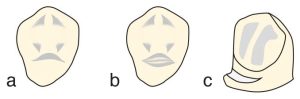

The cingulum rest seats may be prepared in various designs such as “V”, “U or C”, and “flat ledge” types (Figure 10-42).

The “V” rest seat appears crescent-shaped when viewed from the lingual side, extending from one marginal ridge to the other, and is V-shaped when viewed from the proximal surface (Figure 10-44).

The “U” or “C” rest seat is an alternative design to the conventional V-shaped rest seat, suitable for teeth with a prominent cingulum, and features a rest seat shaped like an inverted U or C (Figure 10-46). Preparation starts from one marginal ridge on the lingual surface and proceeds apically toward the cingulum level. As it advances toward the other marginal ridge, the bur rises in the incisal direction. While sufficient depth is achieved, this rest seat design is rarely preferred on enamel because dentin may be exposed.

a) view from the lingual surface, b) view from the incisal surface.